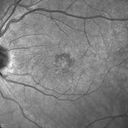

Best Disease Fundus Autofluorescence1234 views00000

(0 votes)

best_maga_13.jpg

Best Disease- Fundus Autofluorescence966 views00000